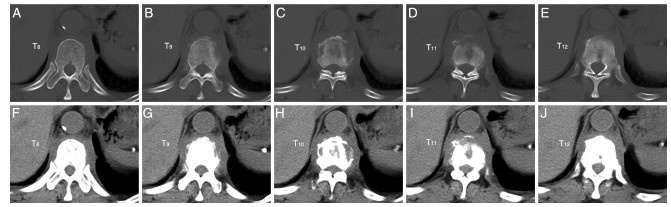

Construction of risk model of esophageal and gastric varices rebleeding in cirrhosis based on 2D-SWE

GUO Li, LOU Junge, YAN Yuanyuan

2025, 23(12): 2042-2045. doi: 10.16766/j.cnki.issn.1674-4152.004287

83 4

Abstract:

Objective  The pathophysiological mechanism of esophageal and gastric varices (EGV) rebleeding in liver cirrhosis is complex, and the mortality rate is high. Identifying the literature factors of EGV rebleeding is important to reduce the mortality rate. Two-dimensional shear wave elastography (2D-SWE) can evaluate the degree of liver hardness and pathological changes in a non-invasive and quantitative manner. This study discusses the construction of the EGV rebleeding risk model based on 2D-SWE to provide a reference for clinical prevention and treatment.  Methods  A total of 162 patients with EGV with cirrhosis admitted to Zhengzhou Central Hospital Affiliated to Zhengzhou University from January 2020 to December 2022 were selected. According to whether rebleeding occurred, the patients were divided into the no rebleeding group (127 cases) and the rebleeding group (35 cases). The risk factors of EGV rebleeding in patients with cirrhosis were analyzed by Logistic regression. To construct a nomogram prediction model for the EGV rebleeding in cirrhotic patients, and evaluate the prediction efficiency of the nomogram model.  Results  The proportion of Child-pugh grade A liver function, the proportion of mild esophageal and gastric varices and the level of ALB in the group without rebleeding were higher than those in the group with rebleeding (P < 0.05), and the proportion of first ligation, liver hardness and spleen hardness in the group with no rebleeding were lower than those in the group with rebleeding (P < 0.05). Logistic multivariate results showed that Child-Pugh grade of liver function, liver hardness, spleen hardness, and ALB were independent influencing factors for EGV rebleeding in cirrhosis (P < 0.05). A nomogram model for predicting EGV rebleeding in cirrhosis was established according to the logistic multi-factor results, and the model was verified. ROC curve analysis results showed that the C-index of the nomogram model was 0.903 (95% CI: 0.846-0.975), and the measured value of the nomogram model was basically consistent with the predicted value, with high predictive value and good clinical effectiveness.  Conclusion  2D-SWE detection of liver and spleen hardness is a risk factor for EGV rebleeding, and the prediction model based on this nomogram has a good predictive effect on EGV rebleeding.